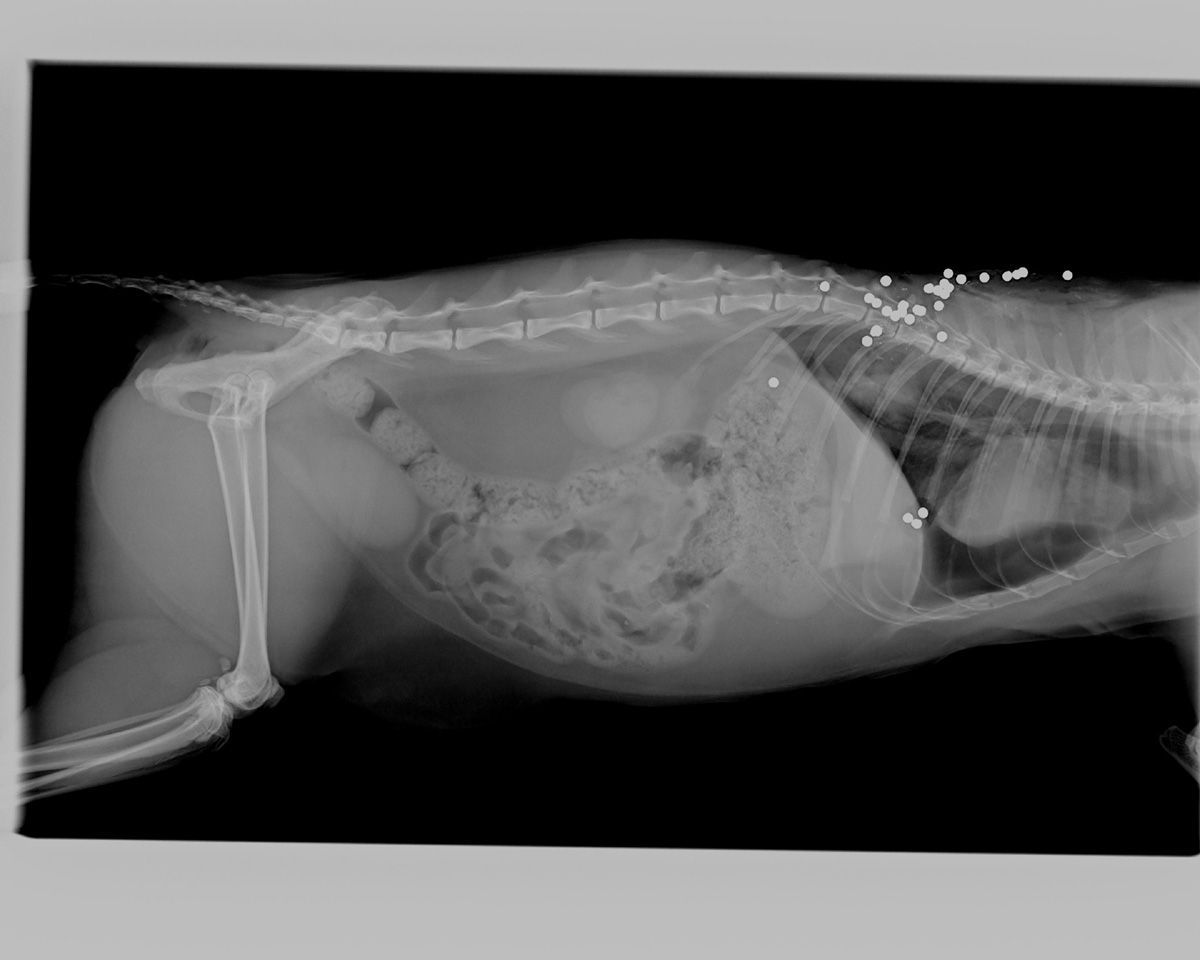

Η γάτα που βλέπετε εντοπίστηκε στις 16 Σεπτεμβρίου το βράδυ πυροβολημένη με κυνηγετικό όπλο στην οδό Μιαούλη στη Λυκόβρυση της Αττικής. Σύμφωνα με τη Γωγώ Φασουλά, στην οποία και ανήκε το ζώο, στο σώμα της γάτας βρέθηκαν 20 σκάγια, τα οποία την άφησαν παράλυτη, ενώ τραυματίστηκε και στον πνεύμονα και δεν μπορούσε εξαιτίας της παράλυσης να ελέγξει την ούρηση και την αφόδευση.

Τα σκάγια όπως φάνηκαν στην ακτινογραφία...

Τα σκάγια όπως φάνηκαν στην ακτινογραφία...

Η κα Φασουλά εξήγησε στο www.zoosos.gr ότι η θηλυκή γάτα τους, η Ναόμη, που ήταν ενάμιση έτους, βγήκε από την αυλή του σπιτιού τους και πυροβολημένη την εντόπισαν οι γείτονες, οι οποίοι και την ενημέρωσαν πως το ζώο έχει τραυματιστεί. Έτσι τη μετέφεραν για περίθαλψη σε κτηνιατρική κλινική του Μιχάλη Φλαράκου στην Κηφισιά. Δυστυχώς αυτόπτες μάρτυρες του εγκλήματος δεν υπάρχουν εντούτοις υποψιάζονται τον δράστη που συχνά δημιουργεί προβλήματα όταν βλέπει ζώα.